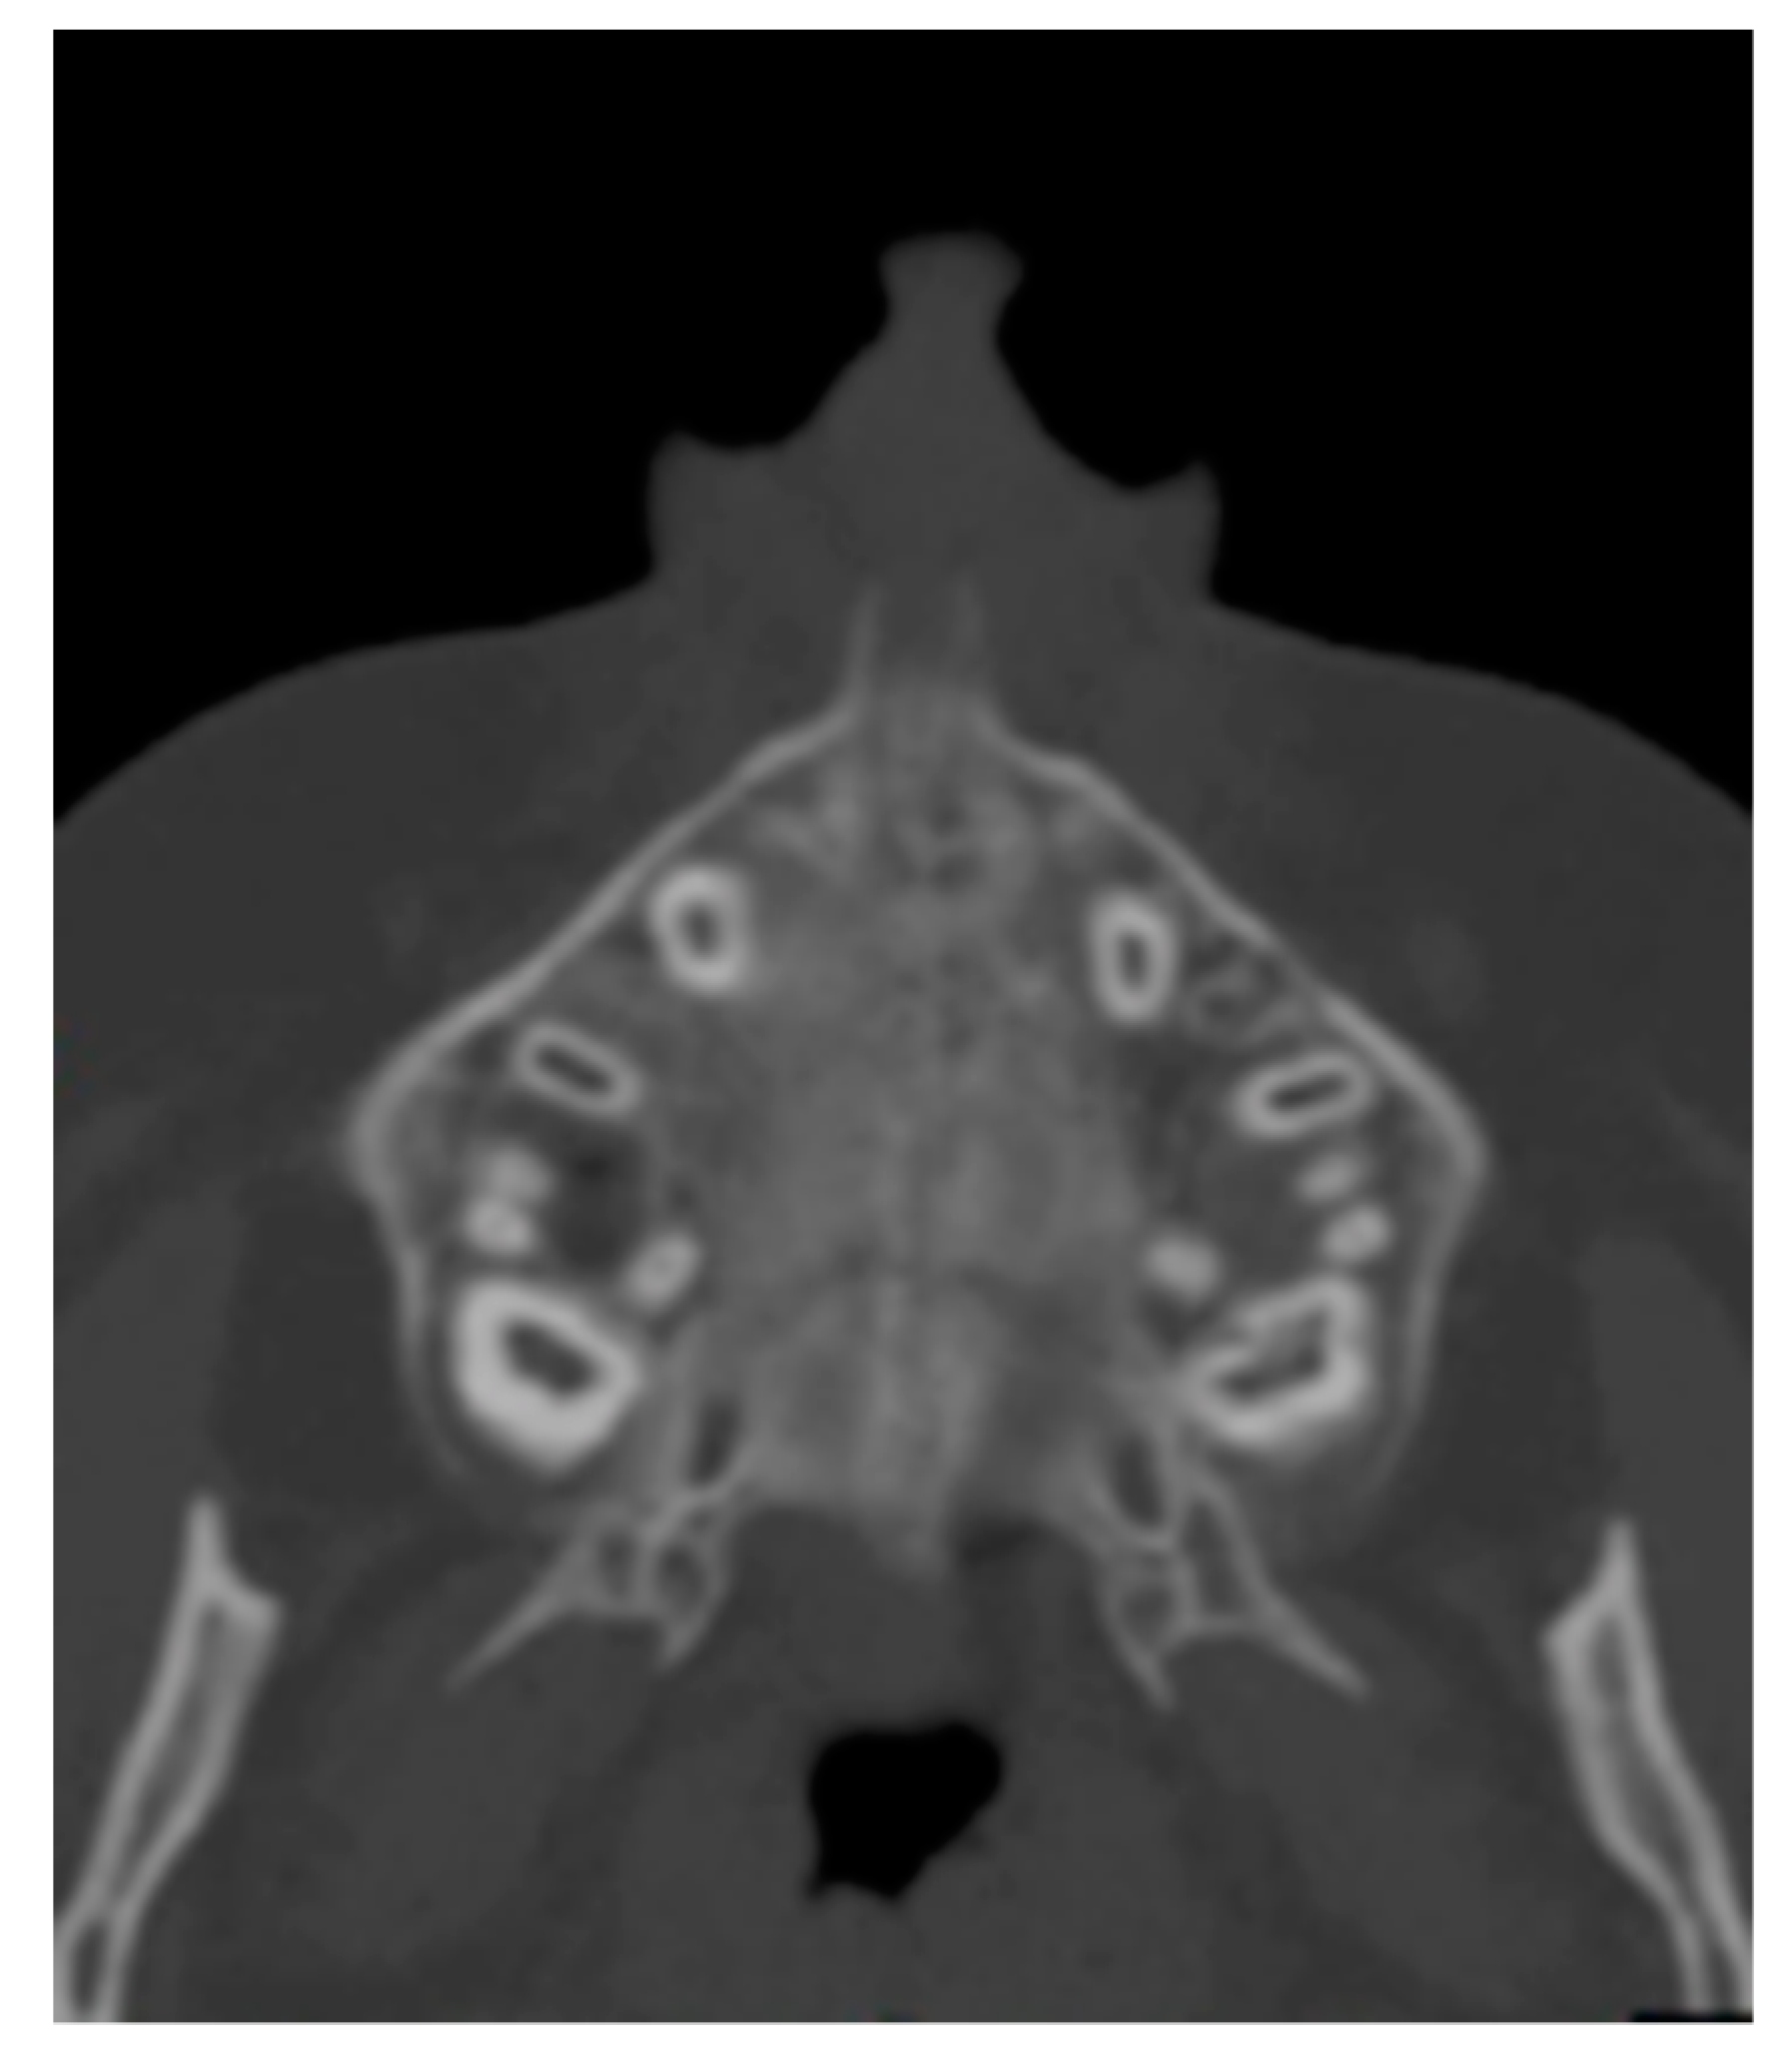

The axial scan passing through hard palate was then identified (Figure 2) and used for all the measurements.

Figure 2. Axial scan.